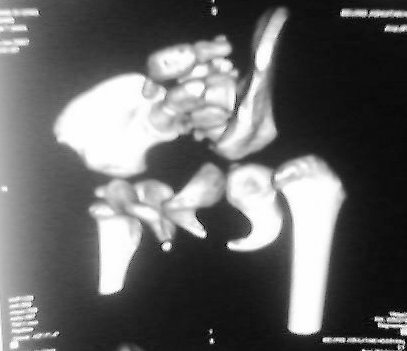

标题: PED0514双胞胎,1岁10个月,走路不稳。

老二:

先天性左侧髋关节脱位。

左侧先天性髋关节脱位.